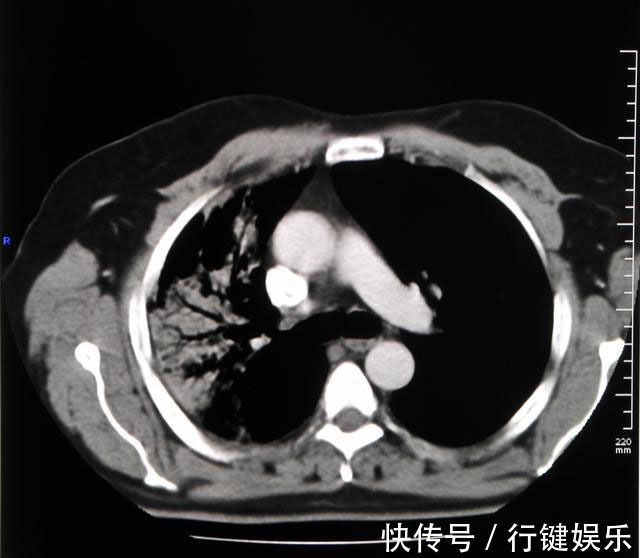

为何会出现这种现象?1.体检项目不对很多单位体检流于形式,仅仅做一些基本检查,比如三大常规、肝肾功能、心电图、上腹部B超、胸片等等,这是最基本的体检套餐。在癌症的筛查中,基本套餐的作用微乎其微。在进行肺部检查时,绝大多数单位体检都是使用胸片,一些偏远地区甚至还在用胸透。我家亲戚当时体检肺部就是做了胸部透视。无论是胸片还是胸透,都是平面的二维图像,就像把人的肺部拍扁形成的影像,不仅分辨率低,很多器官会在这个影像上出现重叠,形成盲区,2cm以内的结节、纵膈或者横膈处的病变有较大的概率会漏诊。而胸透不仅辐射剂量大,而且全凭检查医生肉眼观察数秒,诊断肺癌漏诊率就更高了。如今肺癌诊疗指南都推荐使用低剂量螺旋CT来进行早癌的筛查,选择胸部CT体检不仅可以提高早癌诊断率,还可以降低大约20?肺癌死亡率。此外,一些私立体检机构以盈利为目的,医生水平参差不齐,如果再责任心不强,很有可能会出现漏诊的情况。